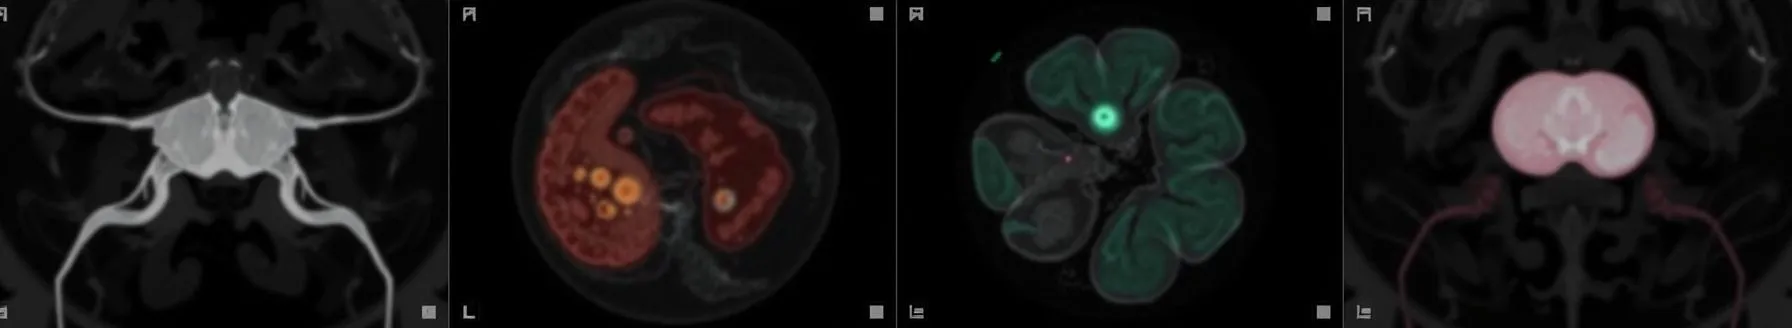

Benign ovarian masses are relatively common, and they encompass a variety of non-cancerous growths in the ovaries.Common benign ovarian masses include functional cysts, dermoid cysts, cystadenomas, and fibromas, each with distinctive features. Symptoms can range from asymptomatic cases to pelvic...

- Ovarian masses are encountered throughout a woman's reproductive life, from childhood to post-menopause. Differentiating between fallopian and ovarian masses via scanning or clinical examination is challenging, leading to the term "adnexal mass." These masses are categorized as ovarian or other types. Ovarian types include functional cysts, functional tumors, neoplastic tumors, and borderline tumors.